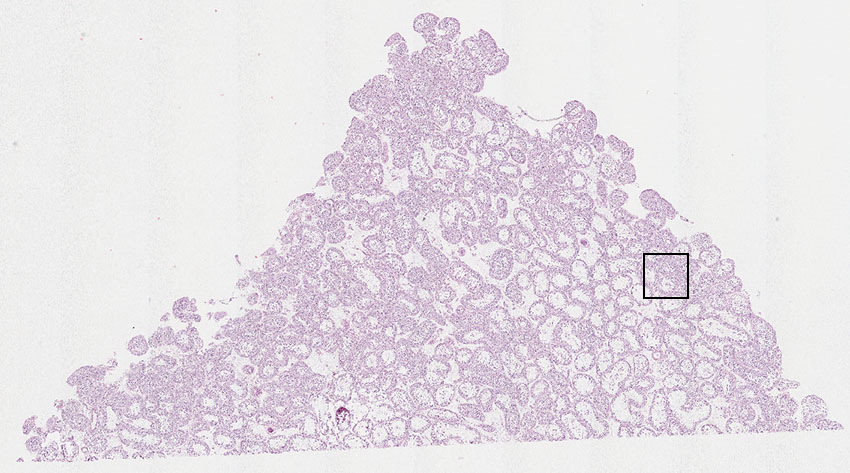

Cells in seminiferous ducts:

55

Other cell types:

45